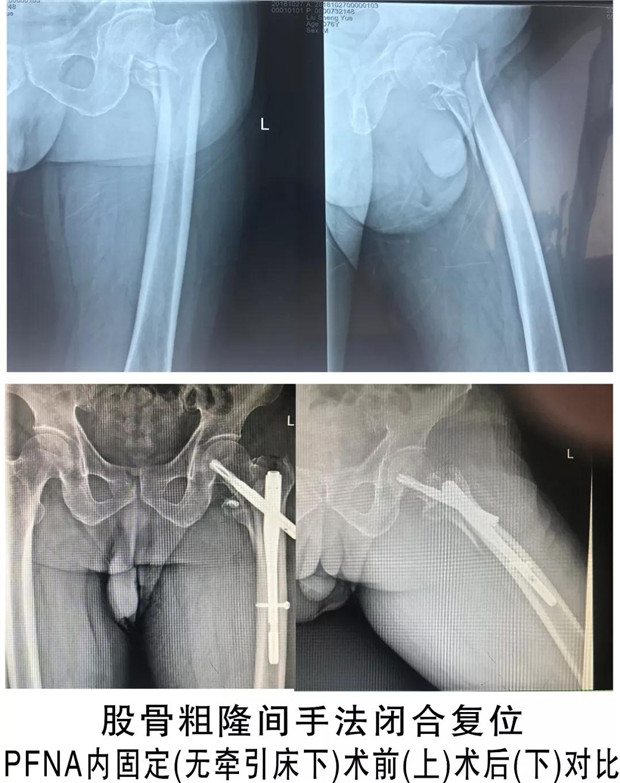

9月底进修结束当天就积极向科室、医务部报道,申请上班。到今天为止,近2个月的工作中,在张永祥主任的带领和指导下,开展了无牵引床下股骨粗隆间骨折的闭合复位PFNA内固定术,手术时间由以前的2个小时缩短到半个小时,术中基本不出血;开展了无专家外援指导下的人工全髋关节置换术、多节段腰椎间盘突出、椎管狭窄的全椎板切除减压、椎管成形、cage植骨内固定术,以及各类复杂的四肢骨折手术。